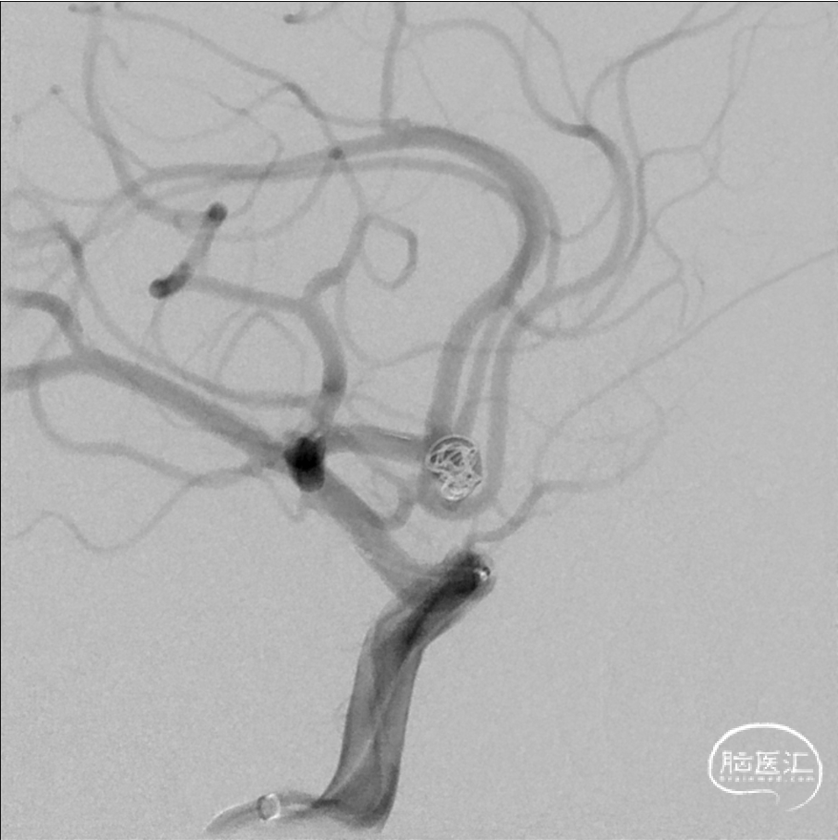

5×15 3D弹簧圈填塞。

再释放1枚3×31 Atlas,再填塞一枚3D 3×8软圈。

4

再先后填塞2枚2D 2×6弹簧圈。